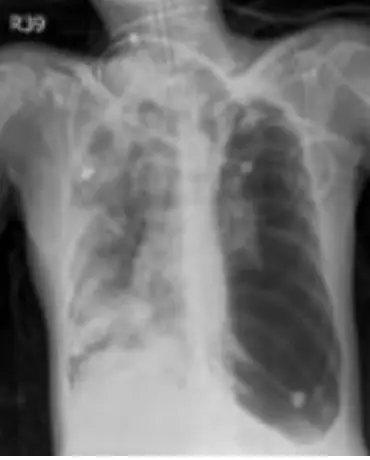

病人的胸部X光如圖(二),病人的身體檢查結果,下列哪一個是最有可能的選項?

從左側胸部 X 光片可見:

- 左側胸腔廣泛透亮(lucency),缺乏肺血管紋理,提示空氣積聚於胸膜腔中(pneumothorax)。

- 左肺邊緣可見塌陷肺緣(visceral pleural line),左側肺葉已明顯塌陷。

- 心臟與縱膈向右側移位(mediastinal shift),符合 tension pneumothorax 造成之壓迫效應。

- 左側橫膈可能下降或平坦,顯示其下壓;右側肺野相對壓迫較小。

此影像與 tension pneumothorax 的典型特徵吻合:大量胸膜腔內氣體、肺臟完全塌陷,伴有向對側的縱膈移位。